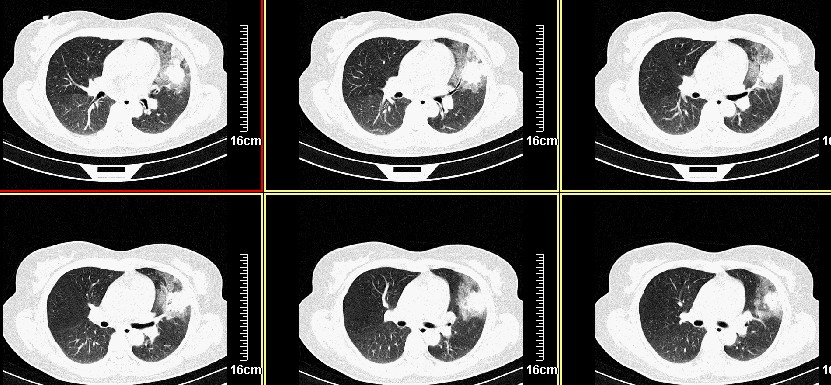

一周之后 复查结果 5mm扫描 40多岁 我们医院的护士

病史?1.首先考虑左肺上叶占位(ca可能);

2.继发型肺tb?

3.单纯感染不除外。

左肺上叶肿块,肺窗周围有“晕征”,纵隔窗有毛刺,临床资料???只能考虑占位???

病灶分明小多多了